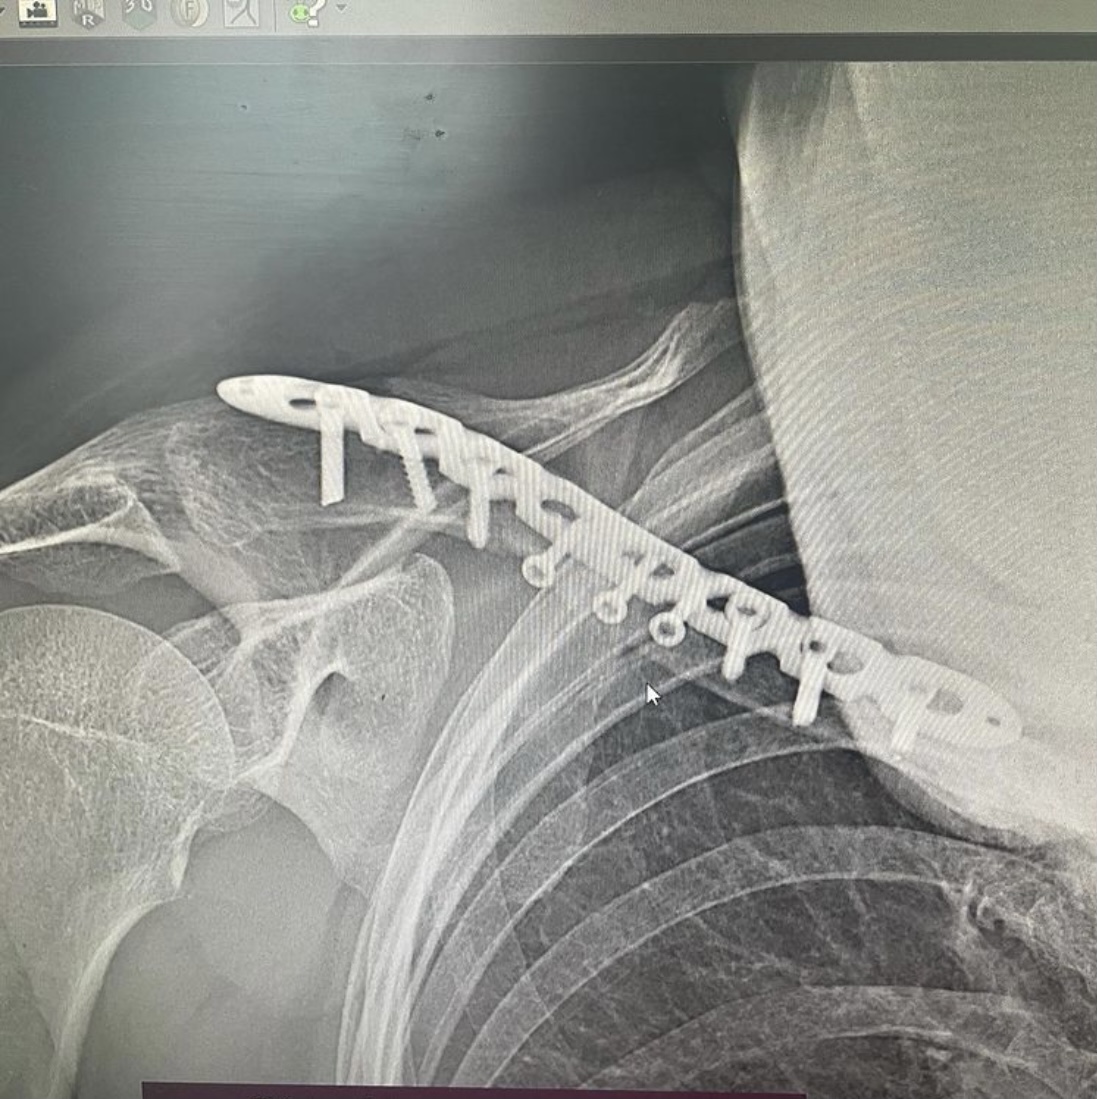

Врач – травматолог – ортопед 7-ой Городской клинической больницы Руслан Ильгизарович Закиров показывает рентген-снимки переломов, которые получили пациенты во время езды на самокате.

Вот снимок мужчины 47 лет, который регулярно пользовался самокатом, поступил в клинику с оскольчатым переломом ключицы. Выполнен остеосинтез пластинной и винтами.